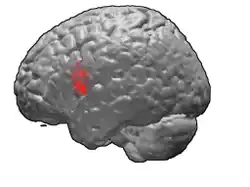

Anatomists such as Paul Broca were able to associate behavioral defects with structural damage to particular parts of the brain. The part of the brain called "Broca's area" was linked to disruption of speech generation without any block in the ability of patients to comprehend language. Broca's area is connected to nearby parts of the brain that contain cells with axons that carry movement control signals to the spinal cord. The bundles of movement control axons degenerate and are smaller than normal in patients with Lou Gehrig's disease.